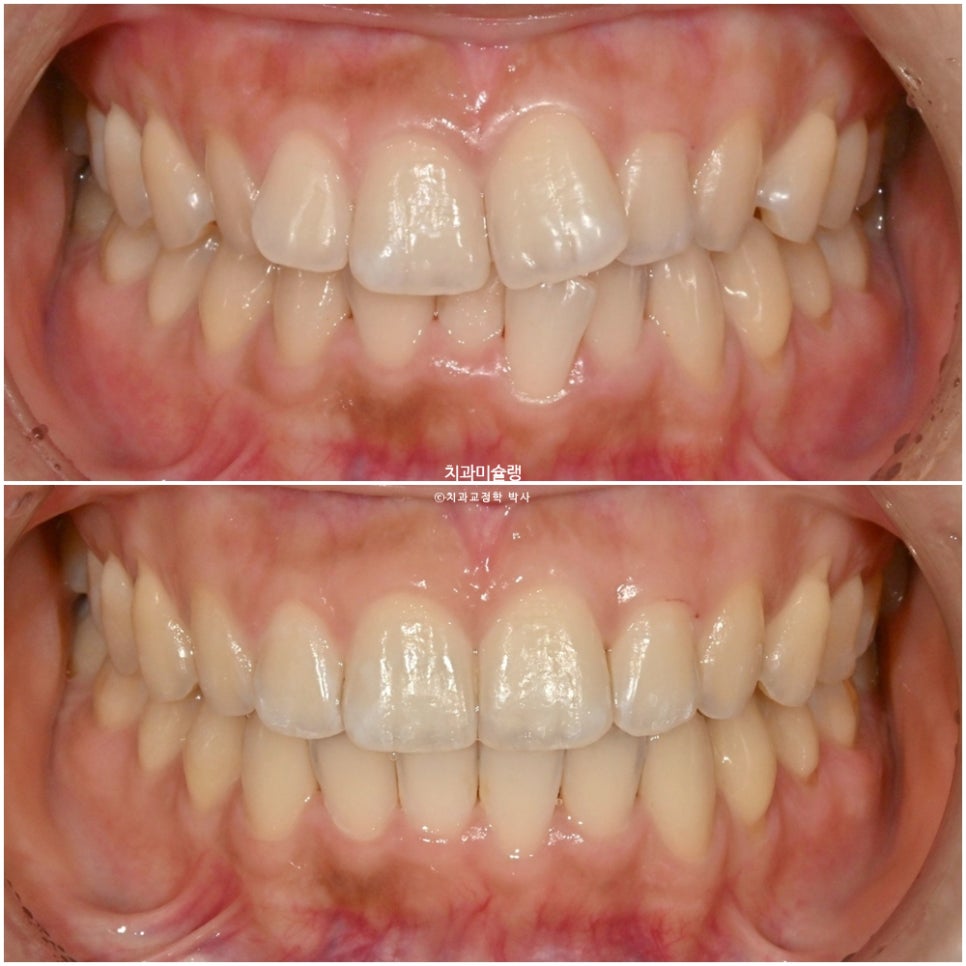

치료 전후 비교

이제 7개월간의 안모 변화를 볼게요.

깔끔해진 미소가 돋보입니다.

안모 전후 스마일 사진에서 보이듯이

통상 치아의 최외곽층 에나멜층의 가장 겉부분에 한정해서 시행하는 면당 최대 0.25mm정도의 치간삭제로는 치아사이즈 변화를 느끼기 힘듭니다.